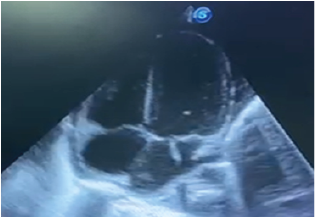

An ankle CT scan is performed urgently and revealed osteoarthritis collected from the right ankle with multiple sequesters of the astragalus (Figure 2).

Figure 2: Scan of the Ankle with A 3D Reconstruction